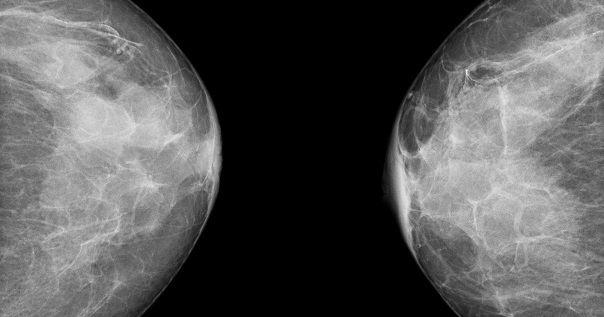

Молочные железы

Онкологическое заболевание молочной железы выявляется чаще остальных видов рака у женщин. Узел в груди можно нащупать самостоятельно. Ежемесячная самодиагностика проводится после завершения месячных. Обнаружение любого уплотнения – повод для визита к специалисту.

Доброкачественные солидные новообразования встречаются значительно чаще злокачественных:

• Фиброаденома – имеет ровные контуры и смещается при надавливании.

• Киста – содержит жидкость внутри и увеличивается в определенные дни цикла.

• Мастопатия – вызывает множественные уплотнения и боль перед началом менструации.

Маммография назначается всем женщинам ежегодно после 40 лет. Исследование фиксирует узлы величиной до 5 миллиметров. Ультразвуковое исследование уточняет картину у молодых пациенток с высокой плотностью железистой ткани. Биопсия устанавливает природу узла и показания к операции.